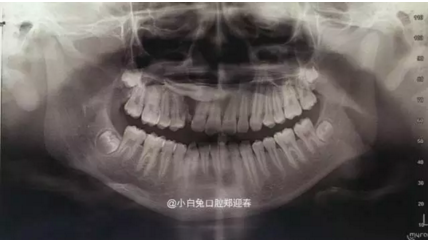

阻生齒外科聯(lián)合正畸治療

27.png

28.png